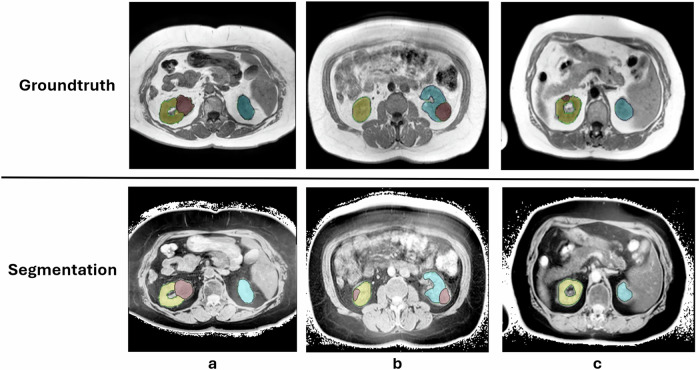

Materials and methods: We retrospectively investigated the performance of two CT-trained models on MRI images: a general multiclass model (TotalSegmentator); and a specialized renal tumor model trained in-house. Both models were applied to 100 T1-weighted (T1w) and 100 T2-weighted fat-saturated (T2wfs) MRI sequences from 100 patients (50 male). Segmentation quality was evaluated on both raw and intensity-inverted sequences using Dice similarity coefficients (DSC), with reference annotations comprising manual kidney tumor annotations and automatically generated segmentations for 24 abdominal structures.

Results: Segmentation quality varied by MRI sequence and anatomical structure. Both models accurately segmented kidneys in T2wfs sequences without preprocessing (TotalSegmentator DSC 0.60), but TotalSegmentator failed to segment blood vessels and muscles. In T1w sequences, intensity inversion significantly improved TotalSegmentator performance, increasing the mean DSC across 24 structures from 0.04 to 0.56 (p < 0.001). Kidney tumor segmentation demonstrated poor performance in T2wfs sequences regardless of preprocessing. In T1w sequences, inversion improved tumor segmentation DSC from 0.04 to 0.42 (p < 0.001).

Conclusion: CT-trained models can generalize to MRI when supported by image augmentation. Inversion preprocessing enabled segmentation of renal cell carcinoma in T1w MRI using a CT-trained model. CT models might be transferable to the MRI domain.